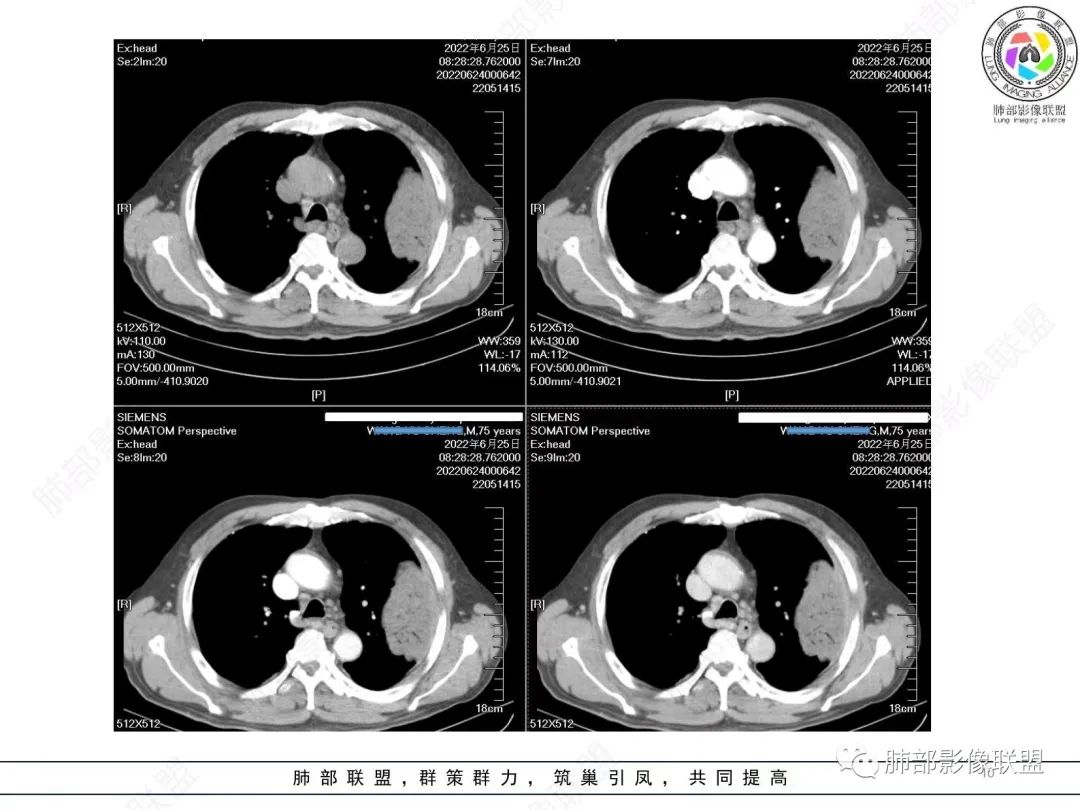

左肺上叶大肿块,膨胀性生长,边界清,密度较低,见部分坏死区,强化弱,肿块见支气管充气V扩张征,分布僵直,枯树枝特点,另一个重要特点血管造影征,淋巴瘤,肿块长轴与胸膜平行,与隐球菌鉴别,隐球荚膜抗原检查,明确诊断经皮肺穿刺。另胸膜钙化(问诊既往有无患胸膜炎病史)。

如果粘液腺Ca,周边太干净了,不支持。

老年男性,糖尿病病史,消瘦、乏力三个月,影像表现左肺上叶胸膜下团块,有一定张力,内部疏松,可见支气管影及坏死区,增强病灶边缘环形强化,内部未见强化,考虑炎性肉芽肿病变,隐球?奴卡?放线菌?鉴别淋巴瘤。

左肺上叶胸膜下肿块,宽基底与胸膜相连,跨叶裂,边缘清晰膨隆,其内支气管充气,部分扩张、僵直,无明显强化,血管造影征,考虑淋巴瘤,鉴别腺癌

左肺胸膜下巨大占位,跨叶裂,宽基底与胸膜相连,胸膜钙化,平扫密度较低,强化不明显,可见内部血管显影,支气管充气征和扩张,考虑为恶性,倾向于淋巴瘤

增强没有强化,血管束正常,气管束有正常有扩张,内有空洞,考虑炎性病变,隐球?

左侧胸腔巨大肿块,跨叶生长,临近胸膜钙化,边缘模糊,可见支气管影,定位肺内,增强后轻度强化,边缘见血管影,考虑淋巴瘤,鉴别肉瘤

老年,明显消瘦,左侧胸廓轻度缩小?胸膜增厚,见钙化,以前结核?接触其他?整个肿块膨隆,坏死不明显,支气管通畅,轻度扩张轻度强化,考虑恶性,淋巴瘤可能

左肺上叶胸膜下肿块,膨胀性生长,边界清晰,密度不均部分坏死,未见强化,病灶内支气管迂曲扩张,病灶长轴与胸膜平行,胸膜下脂肪间隙存在,胸膜钙化,考虑放线菌?毛霉?鉴别淋巴瘤

支持淋巴瘤,左上肺大肿块,有分叶,边缘光整,病灶内密度不均,可见支气管扩张征,增强后可见血管影征。周围肺野清晰。

左肺上叶肿块,宽基底与胸膜相连,跨叶裂,边缘清晰膨隆,可见小分叶,其内支气管充气,部分扩张、僵直,呈枯枝征,支气管达边征,增强无明显强化,可见血管造影征,考虑恶性病变,淋巴瘤,鉴别粘液腺癌。

左肺团块样病灶,分叶,膨隆,不规则空洞,支气管枯枝样,血管造影征,考虑恶性,腺癌(肺肠型)。